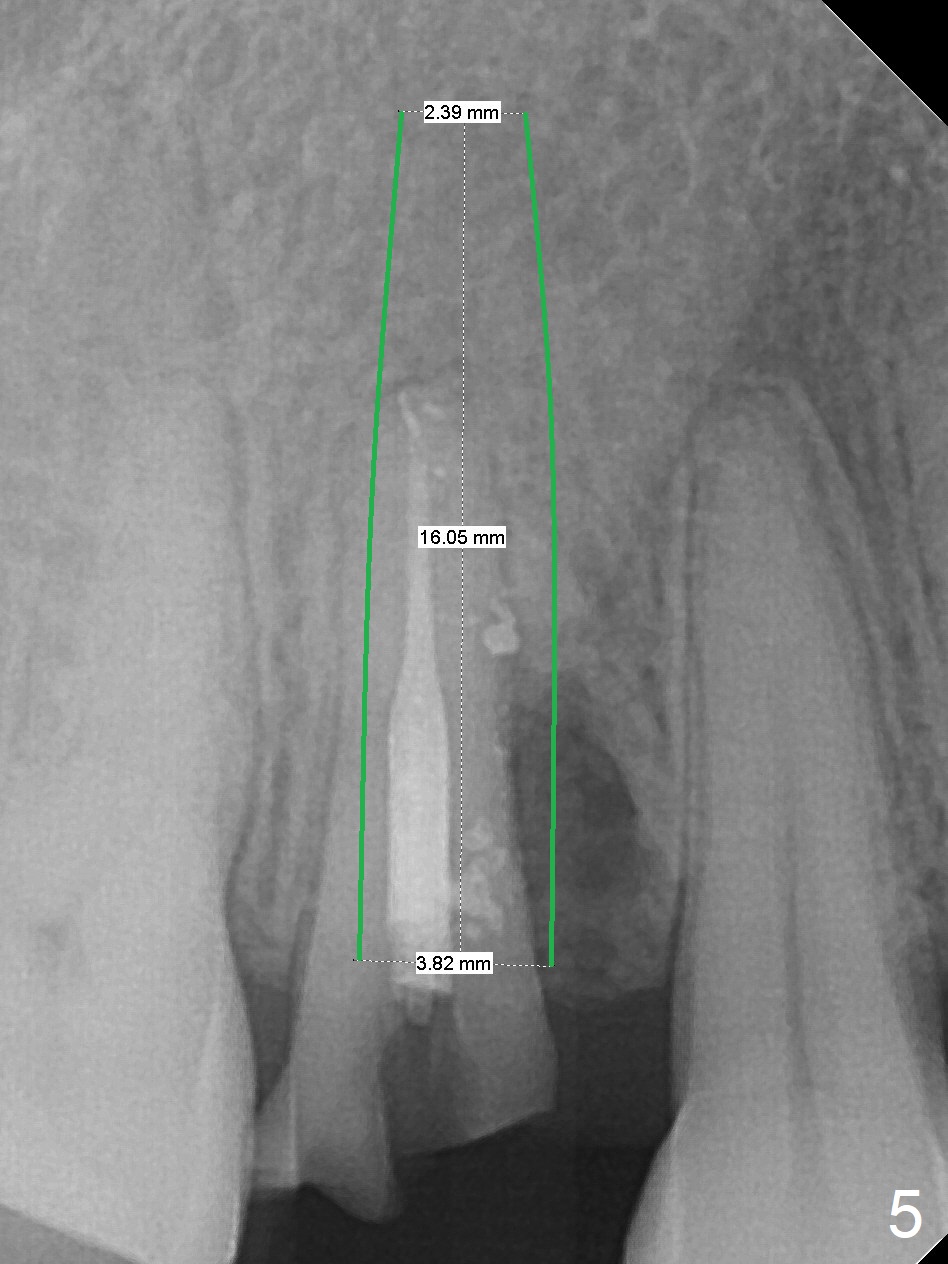

Seven years post RCT (Fig.1), the tooth #4 of a 65-year-old woman fractures subgingival palatally (Fig.2). Since the root of the affected tooth is close to the tooth #3, osteotomy is established in the mesial slope of the socket (Fig.3). Change the trajectory once the drill has penetrated the lamina dura of the socket (Fig.4). The initial depth will be 20 mm for a 3.8x16 mm implant (Fig.5).